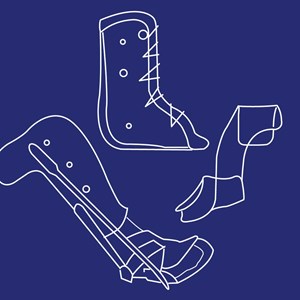

Knæ-Ankel-Fod Ortose (KAFO)

Type: pdf

Størrelse: 1539 KB